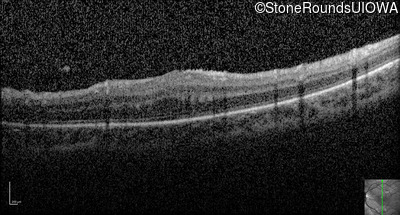

Optical Coherence Tomography - Left - 20/80

Exemplar / OCT Stack